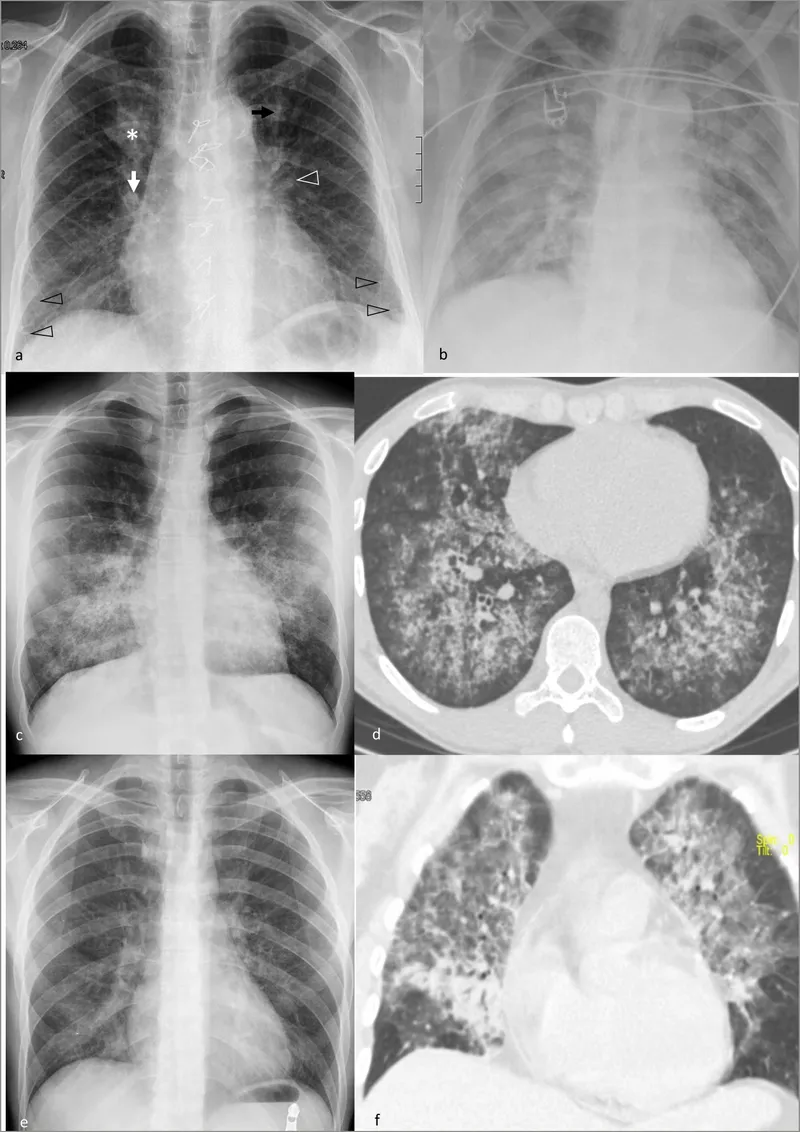

⭐ High-Yield: Chest X-ray classically shows diffuse, bilateral ground-glass opacities or "bat-wing" appearance.

- Chest X-ray classically shows diffuse, bilateral interstitial infiltrates or ground-glass opacities.